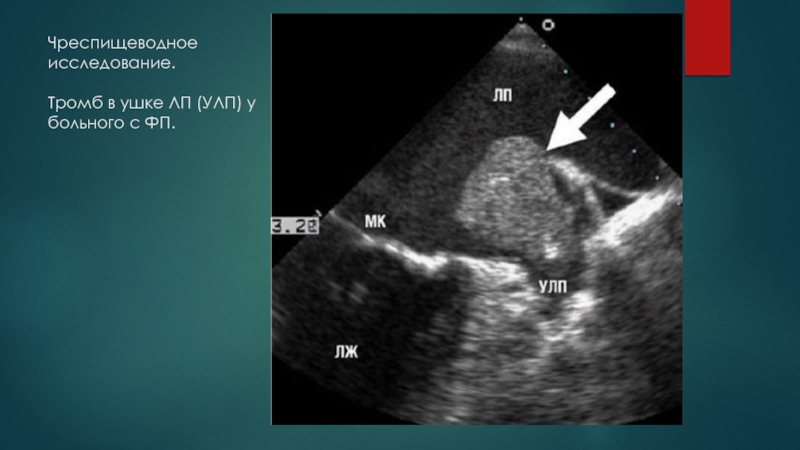

Слайд 28Чреспищеводное исследование.  Тромб в ушке ЛП (УЛП) у больного с ФП.

Чреспищеводное исследование.   Тромб в ушке ЛП (УЛП) у больного с ФП.

Альтернативой длительной антикоагуляции (особенно при применении НОАК) перед плановой кардиоверсии служит исключение тромба в ЛП и/или его ушке с помощью ЧПЭХОКГ.